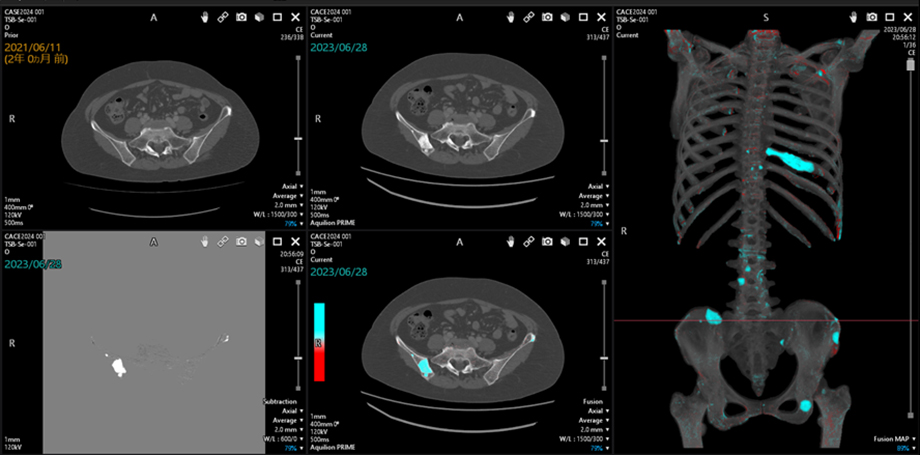

しかし、CTによるフォローアップ検査では、がんがあった部位や転移が多いとされる臓器、リンパ節などの確認が優先され、骨転移はなかなか気づきにくいという問題があるとされています。しかも、骨は頭から足先まで全身に多数あり、CT画像も膨大な量になります。そこで、京都大学とキヤノンが目指したのは、CT画像から骨の経時変化を可視化できるシステムです。転移の発見においては、過去と現在のCT画像を比較して、その違いを見出すことが基本となります。そのわずかな画像の違いを差分画像として表示することで、骨転移の発見を支援します。

差分画像を作成する上で重要となるのが、過去と現在の画像との正確な位置合わせです。CT撮影では、患者さんが毎回、同じ体型、姿勢で検査を受けるとは限らず、さらに息の吸い方一つで画像が変わってしまいます。

そこで、形状が変わる被写体の画像の位置ずれを補正する技術として、すでに医用画像や衛星画像の解析で用いられていた位置合わせ技術をCTに応用することを坂本先生が提案しました。これは、画像を変形させて位置を合わせていく方法です。まず、腰の高さや曲がり具合など明らかに過去画像と異なる骨の部位について、画像を変形させて大まかな位置合わせを行います。そのあと、体位によって変化しにくい胴体部分と変化しやすい手足など胴体以外の部分に分類し、それぞれの画像を変形させて細かく位置を合わせていきます。そして最後に、画像を統合し、残りのノイズを除去する処理を組み込み、撮影条件が異なる画像間でも骨の変化が明確にわかる差分画像を生成します。しかし、実際の臨床で用いるには、画像処理の高速化と位置合わせの高精度化が不可欠でした。

京都大学とキヤノンは、独自のアルゴリズム開発や画像処理の工夫などを重ね、撮影条件が異なる画像でも、骨の経時変化に特化した差分画像を生成する位置合わせ技術を開発しました。加えて、差分画像に脊椎や肋骨位置を表示するラベリング技術も実現。これらの技術により、病変の存在する部位の確認が容易になりました。実際にこのシステムを用いたことで、読影時間が3分の1に短縮されたケースが報告されています。